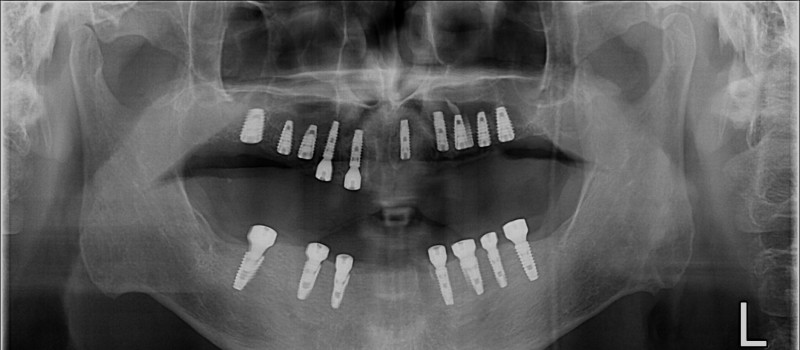

무치악 임플란트 회복

Before

무치악 임플란트 회복 Full Mouth Rehabilitation